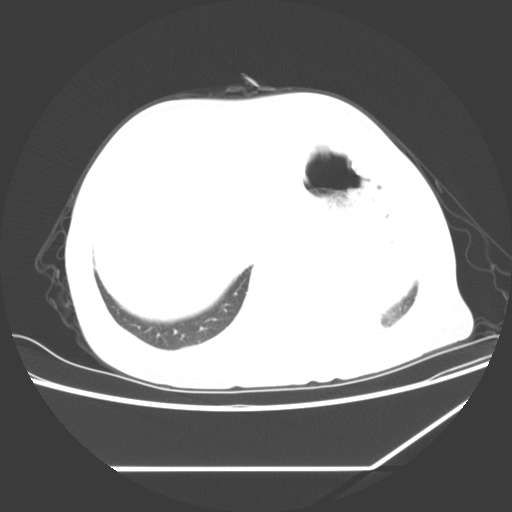

1、左肺中央型肺癌并双肺弥漫性转移   2、双肺部感染    3、肺大泡     4、左侧胸腔积液

双侧肺弥漫性病变,可见“空泡征”及“蜂窝征”,考虑肺泡癌可能性大,左侧胸腔积液,考虑胸膜受累可能!

1)不排除肺泡癌可能。2)左侧胸腔积液。